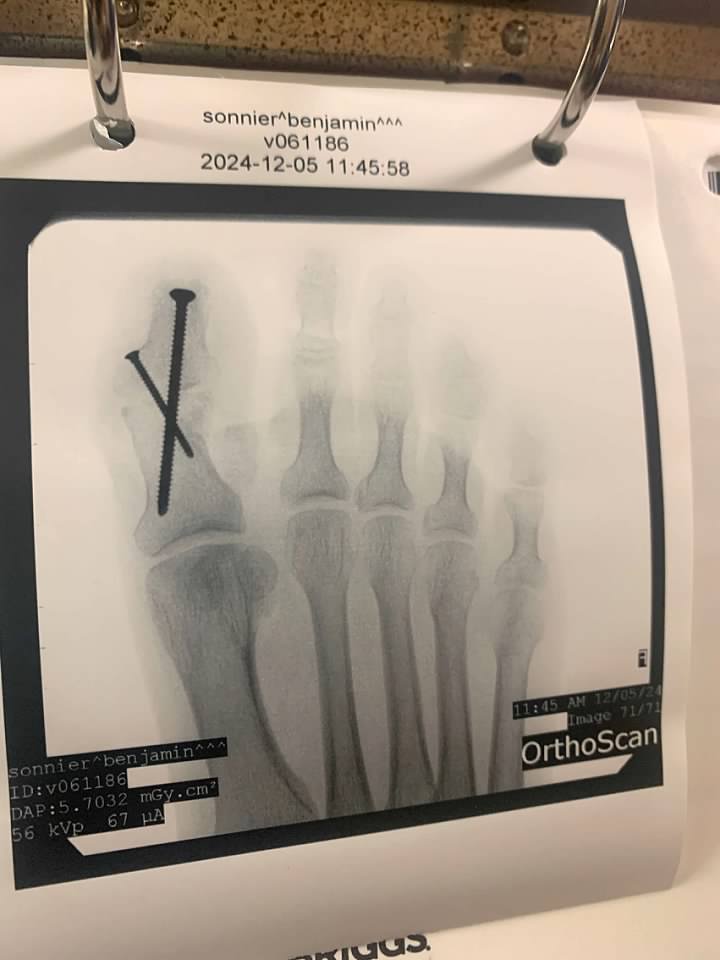

The surgeon went in under his foot and released some tendons, went in under his toes and worked on the capsules and this straightened them out.  His big toe was curled in an excessive fashion.  The tendons were cut and lengthened and using screws, the big toe was straightened out as well.